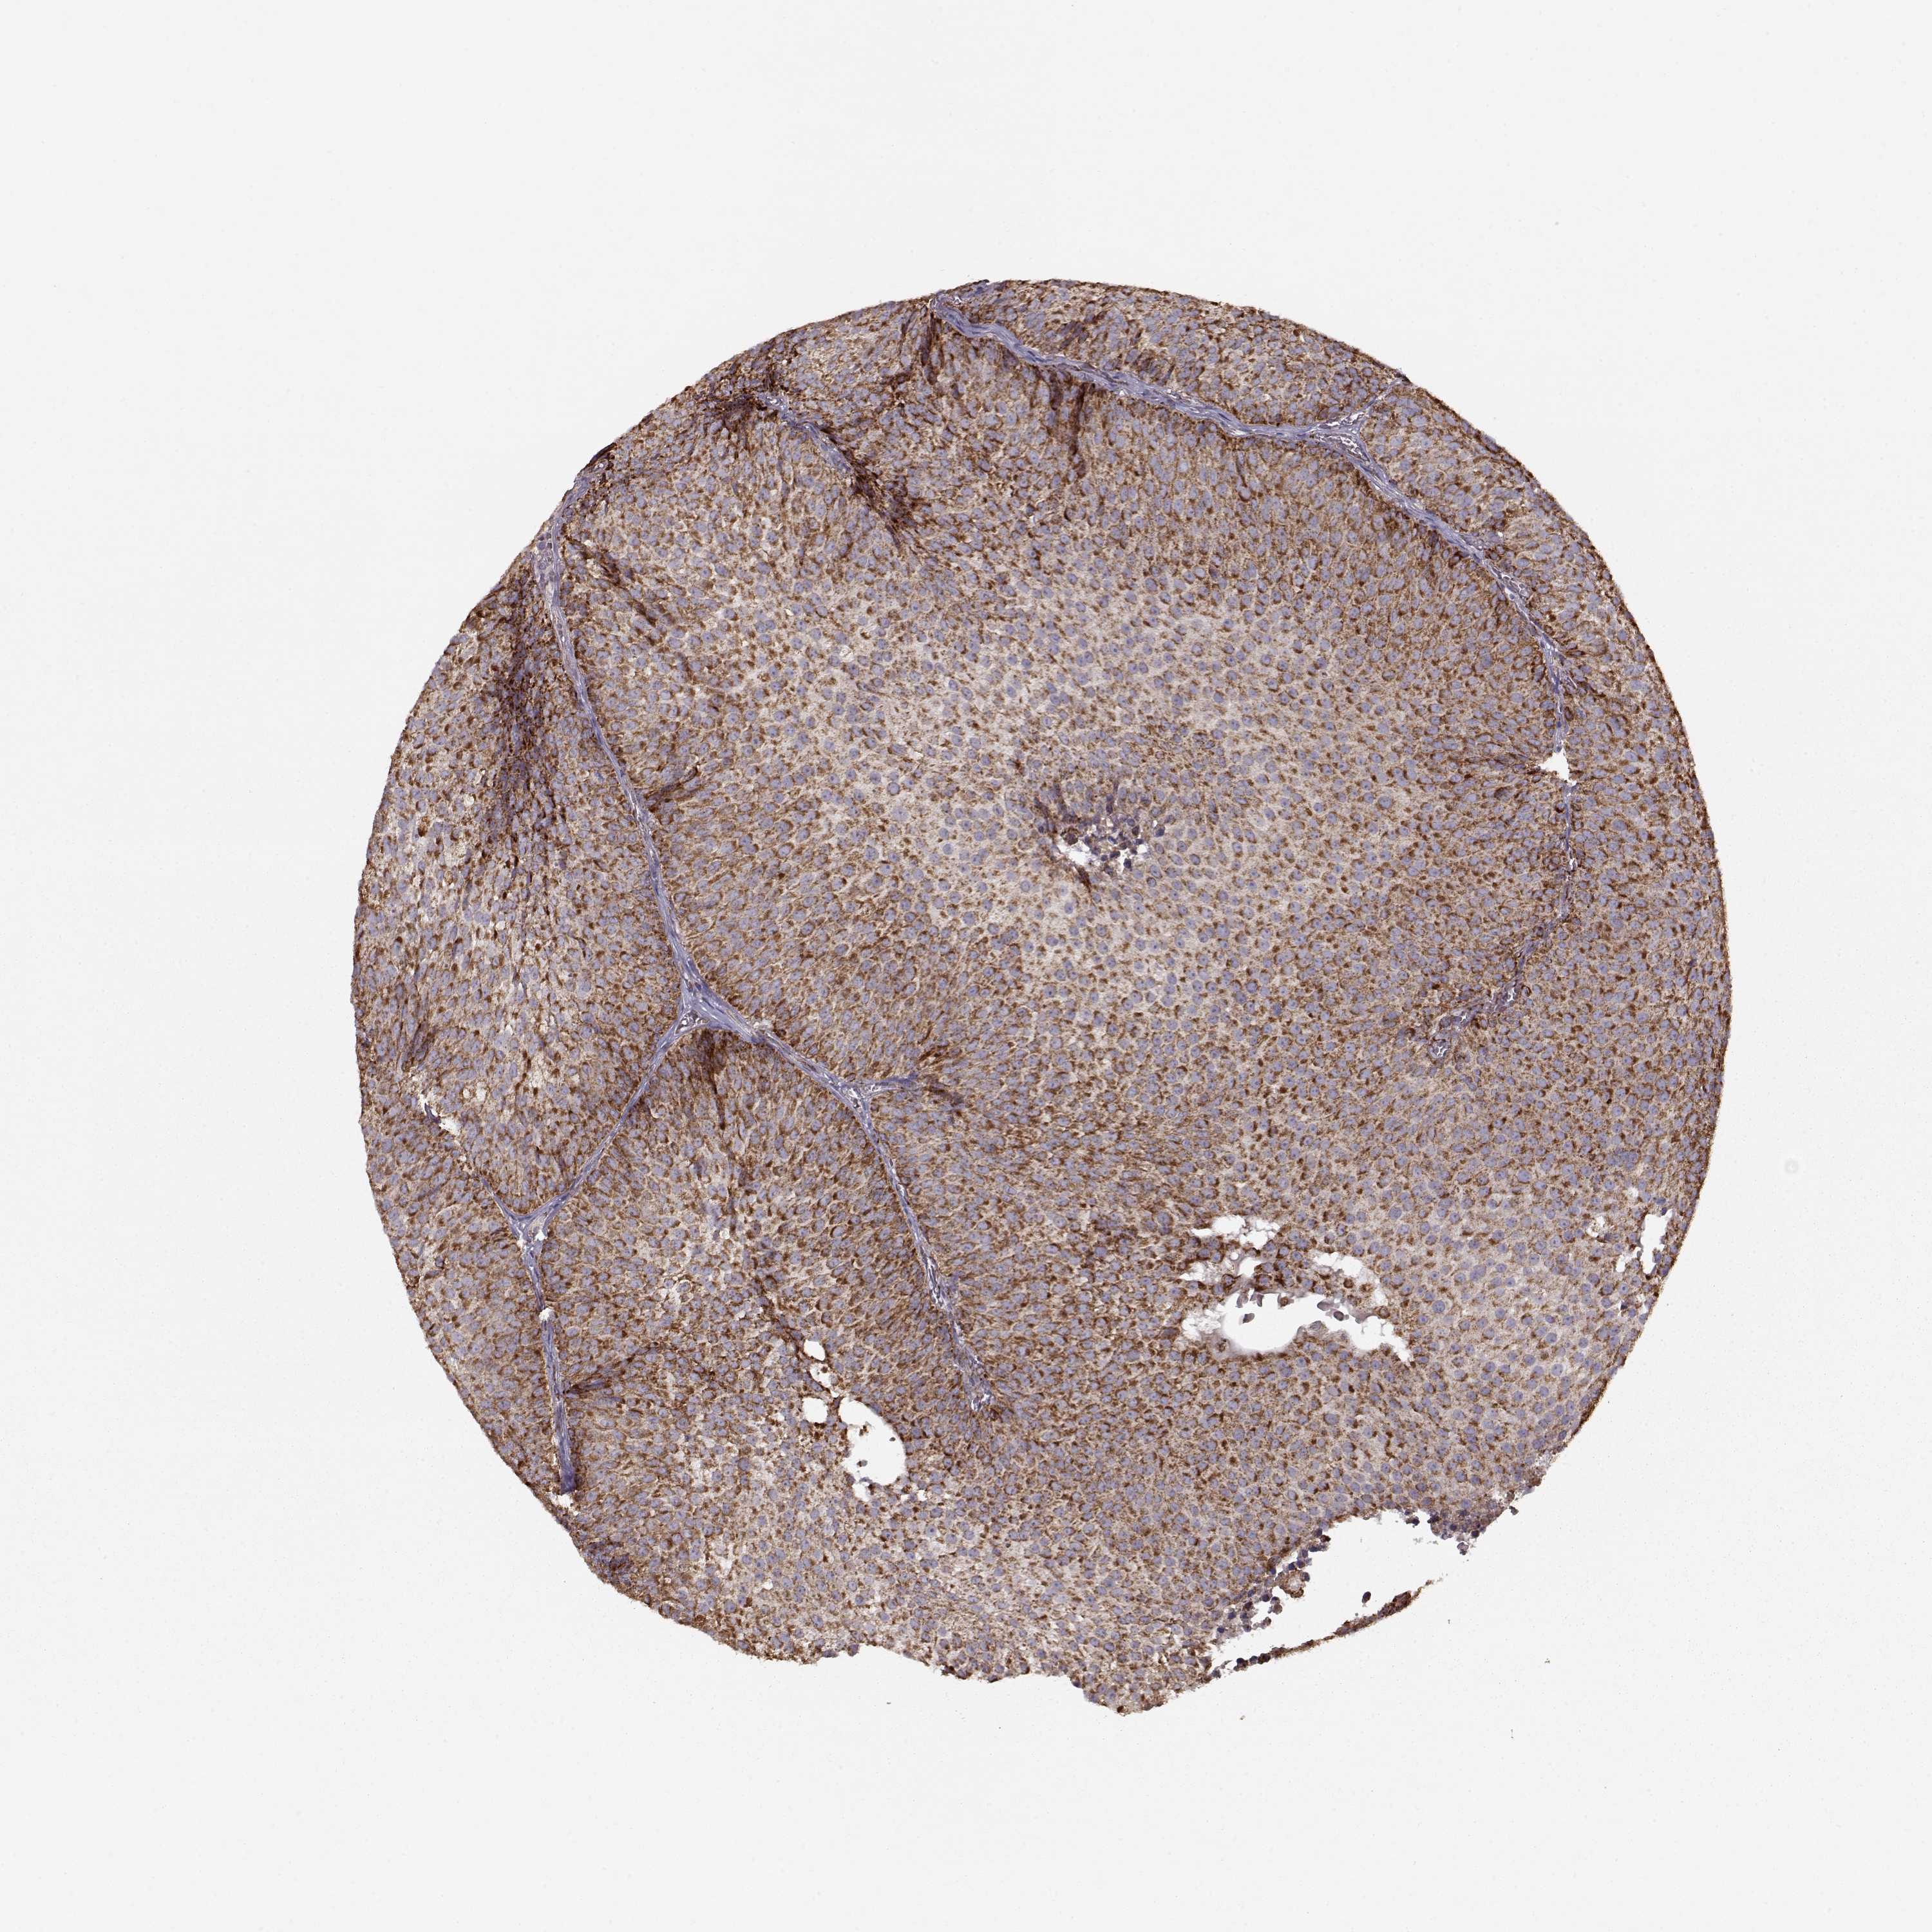

UROTHELIAL CANCER - Protein expressioni

A mouse-over function shows sample information and annotation data. Click on an image to view it in a full screen mode. Samples can be filtered based on level of antibody staining by selecting one or several of the following categories: high, medium, low and not detected. The assay and annotation is described here.

Antibody stainingi

Antibody staining in the annotated cell types in the current human tissue is reported as not detected, low, medium, or high, based on conventional immunohistochemistry profiling in selected tissues. This score is based on the combination of the staining intensity and fraction of stained cells.

Each image is clickable and will lead to virtual microscopy that enables deeper exploration of all samples and also displays staining intensity scores, fraction scores and subcellular localization as well as patient and tissue information for each sample.

Antibody HPA072695

Staining

High

Medium

Low

Not detected

Intensity

Strong

Moderate

Weak

Negative

Quantity

>75%

75%-25%

<25%

None

Location

Nuclear

Cytoplasmic/membranous

Cytoplasmic/membranous,nuclear

Urothelial carcinoma, High grade

Urothelial carcinoma, NOS

Urothelial carcinoma, Low grade